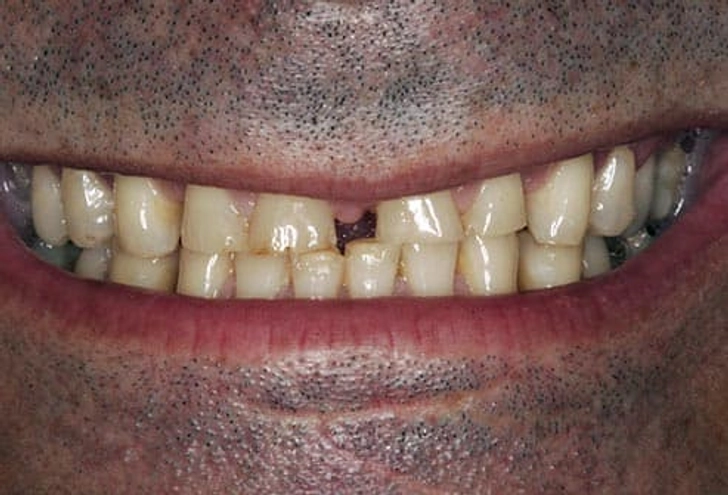

۱۰. فاصله بین دندانها (گپ یا دیاستم بین دندانها)

برخی افراد فاصله بین دندانهای جلویی خود را دوست دارند، اما اگر بخواهید آن را اصلاح کنید، گزینهها شامل ارتودنسی، کامپوزیت ونیر یا لمینیت است.

۸. تعداد زیاد دندانها (Hyperdontia)

بهطور معمول هر فرد ۲۰ دندان شیری و ۳۲ دندان دائمی دارد. اما برخی افراد دندان اضافی دارند که به آن هایپردانتیا میگویند. این وضعیت گاهی همراه با مشکلاتی مانند شکاف کام یا سندرم گاردنر است. درمان شامل کشیدن دندانهای اضافی و درمان ارتودنسی برای اصلاح بایت است.